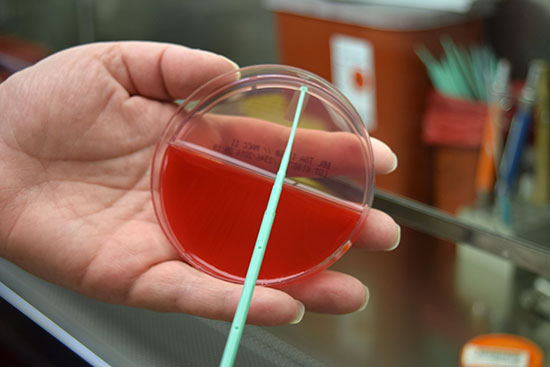

- Blood sampling from the heart, tail vein, jugular vein and ocular sinus